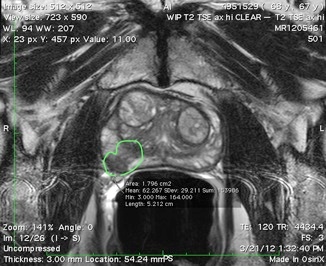

The MRI images below are from an actual case from the Scionti Prostate Center

Diagnosis

55 year old male with elevated PSA. The MRI shows a tumor in the prostate (outlined in green). Artemis MRI-guided biopsy revealed Gleason Grade 7 cancer. The standard ultrasound guided (random) biopsies were all benign (missed the cancer)